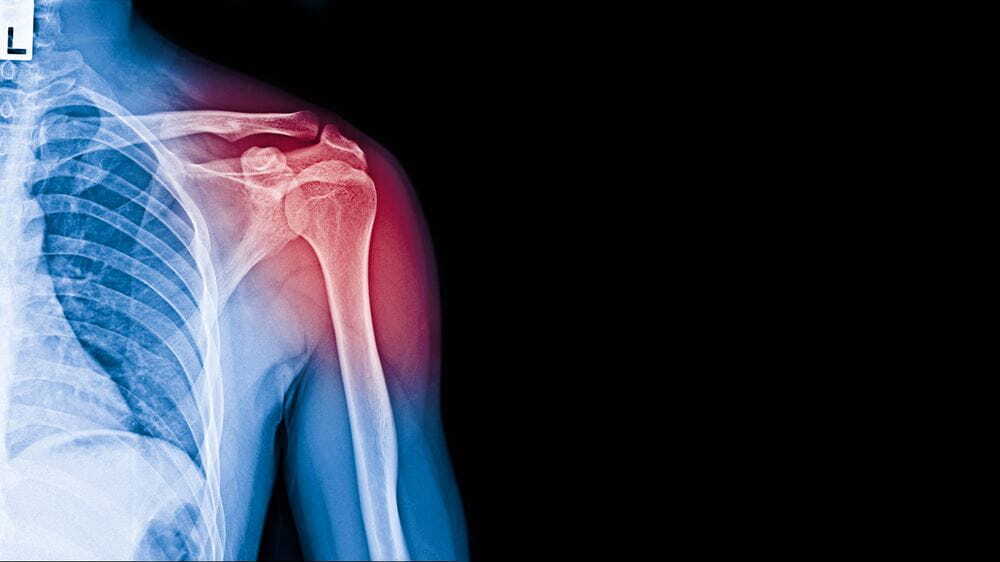

어깨뼈 골절의 모든 것: 통증부터 재활까지

어깨뼈 골절은 그 심각성과 복잡성에 따라 다양한 치료와 재활 과정을 요구합니다. 본문에서는 어깨뼈 골절의 통증 기간, 상완골 골절의 입원 기간, 수술 후의 물리치료와 도수치료에 대해 자세히 알아보겠습니다. 또한, 이 모든 치료 과정이 어떻게 진행되며, 실비보험은 어떤 부분을 커버하는지에 대해서도 설명드립니다.

어깨뼈 골절 시 통증은 매우 개인적인 요소로, 환자의 상태와 골절의 정도에 따라 크게 달라질 수 있습니다. 통증 관리는 주로 처음 며칠 동안 강력한 진통제를 사용하여 관리되며, 이는 골절 부위의 안정화와 통증의 감소에 도움을 줍니다. 초기에는 심한 통증을 경험할 수 있지만, 대부분의 경우 이는 점차 감소합니다.

상완골 골절은 어깨 부위에서 발생할 수 있는 또 다른 유형의 골절로, 입원 기간은 대체로 2주에서 3주 사이입니다. 그러나 교통사고와 같은 중대한 사고의 경우 더 긴 입원이 필요할 수 있으며, 수술 후 항생제 투여와 같은 추가적인 치료로 인해 입원 기간이 연장될 수 있습니다.